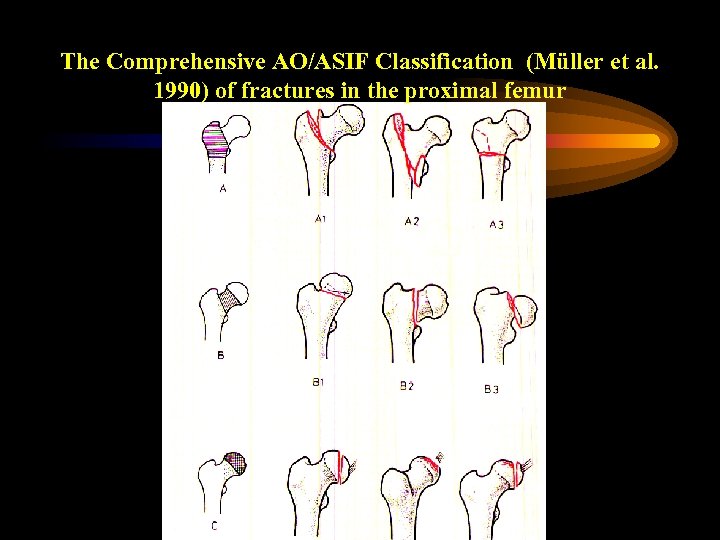

The Comprehensive AO/ASIF Classification (Müller et al. 1990) of fractures in the proximal femur

The Comprehensive AO/ASIF Classification (Müller et al. 1990) of fractures in the proximal femur